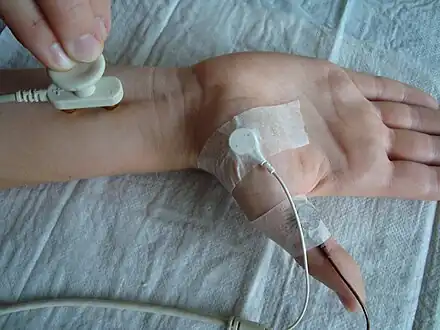

Diagnostic procedures that may reveal muscular disorders include direct clinical observations. This usually starts with the observation of bulk, possible atrophy or loss of muscle tone. Neuromuscular disease can also be diagnosed by imaging, various blood tests and using electrodiagnostic medicine tests[19] including electromyography[20] (measuring electrical activity in muscles) and nerve conduction studies.[21] Genetic testing is an important part of diagnosing inherited neuromuscular conditions.[19]

Nerve conduction velocity (study)

Nerve conduction velocity (study)